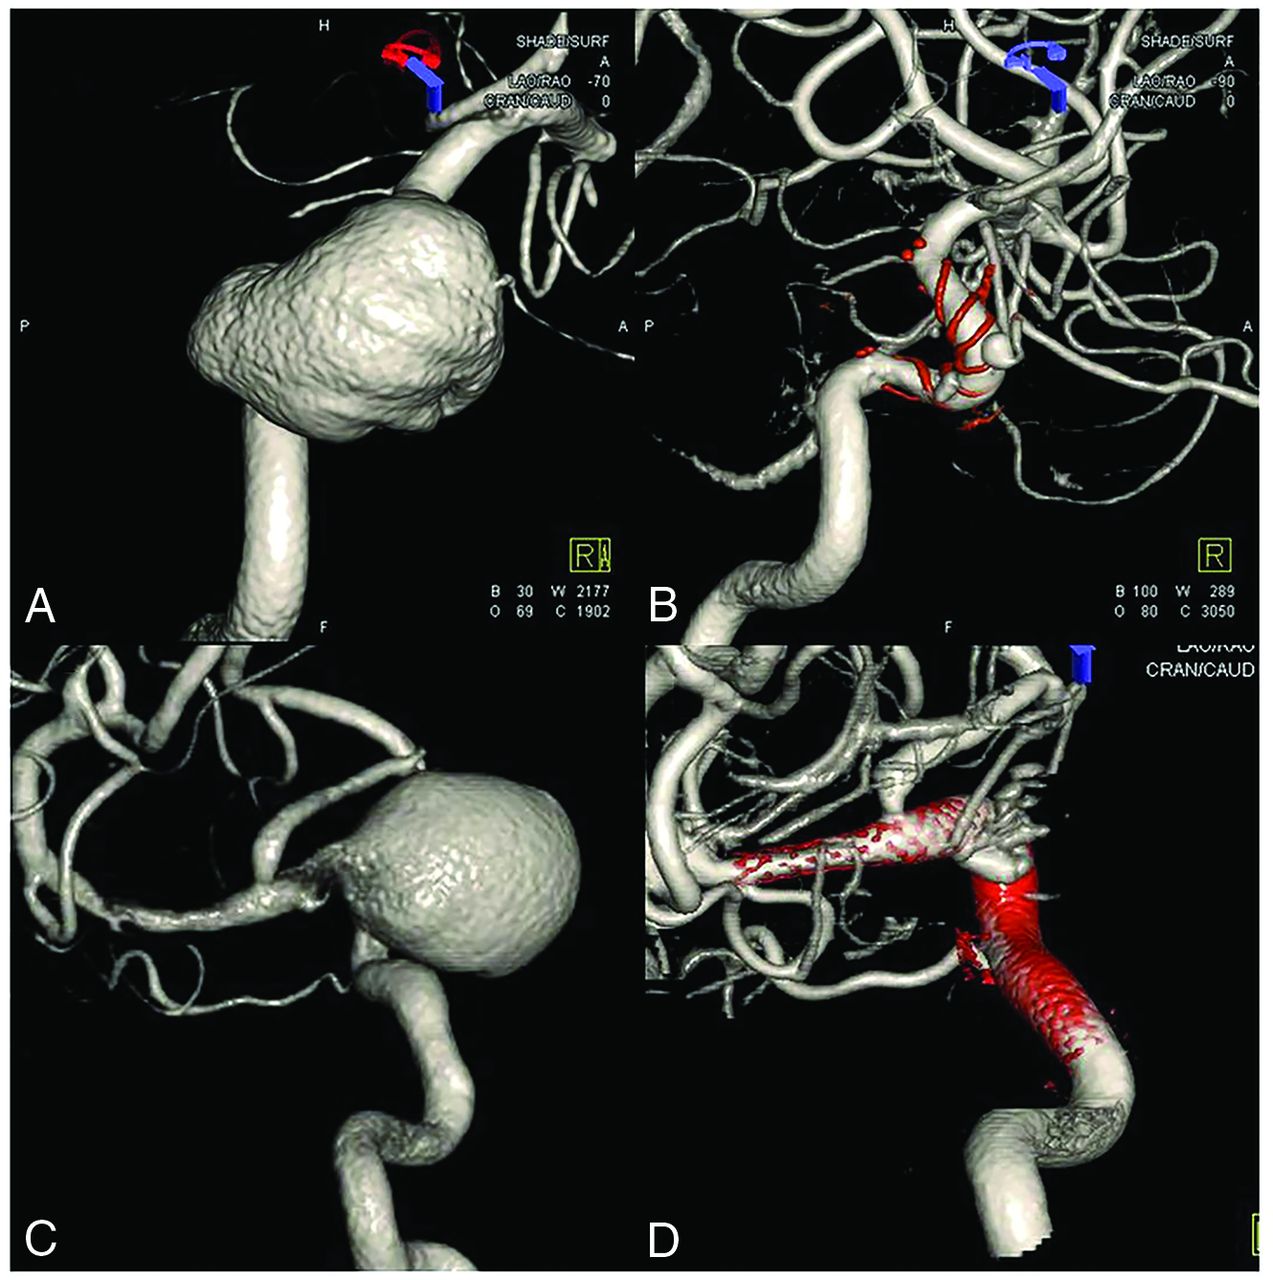

In this study, it was confirmed that the presence of incorporated vessels (OR = 0.13, P = .021) was a significant factor in predicting the effects of FD. Among cases with no incorporated vessel, 22/29 (75.8%) showed the effect of FD, whereas in cases with incorporation, only 12/22 (54.6%) cases showed the effect of FD. In patients exhibiting remnant entry or subtotal filling on follow-up angiography, a significant proportion of aneurysms developed thromboses and occlusion, but sometimes remnant aneurysms were apparent close to the incorporated vessels (Fig 2). Bender et al12 studied a single-institution series of 445 cases and reported that vessel incorporation was a risk factor for incomplete occlusion after FD (OR = 2.206, P = .035).

Remnant aneurysms are apparent close to the incorporated ophthalmic artery on 6-month follow-up angiography.